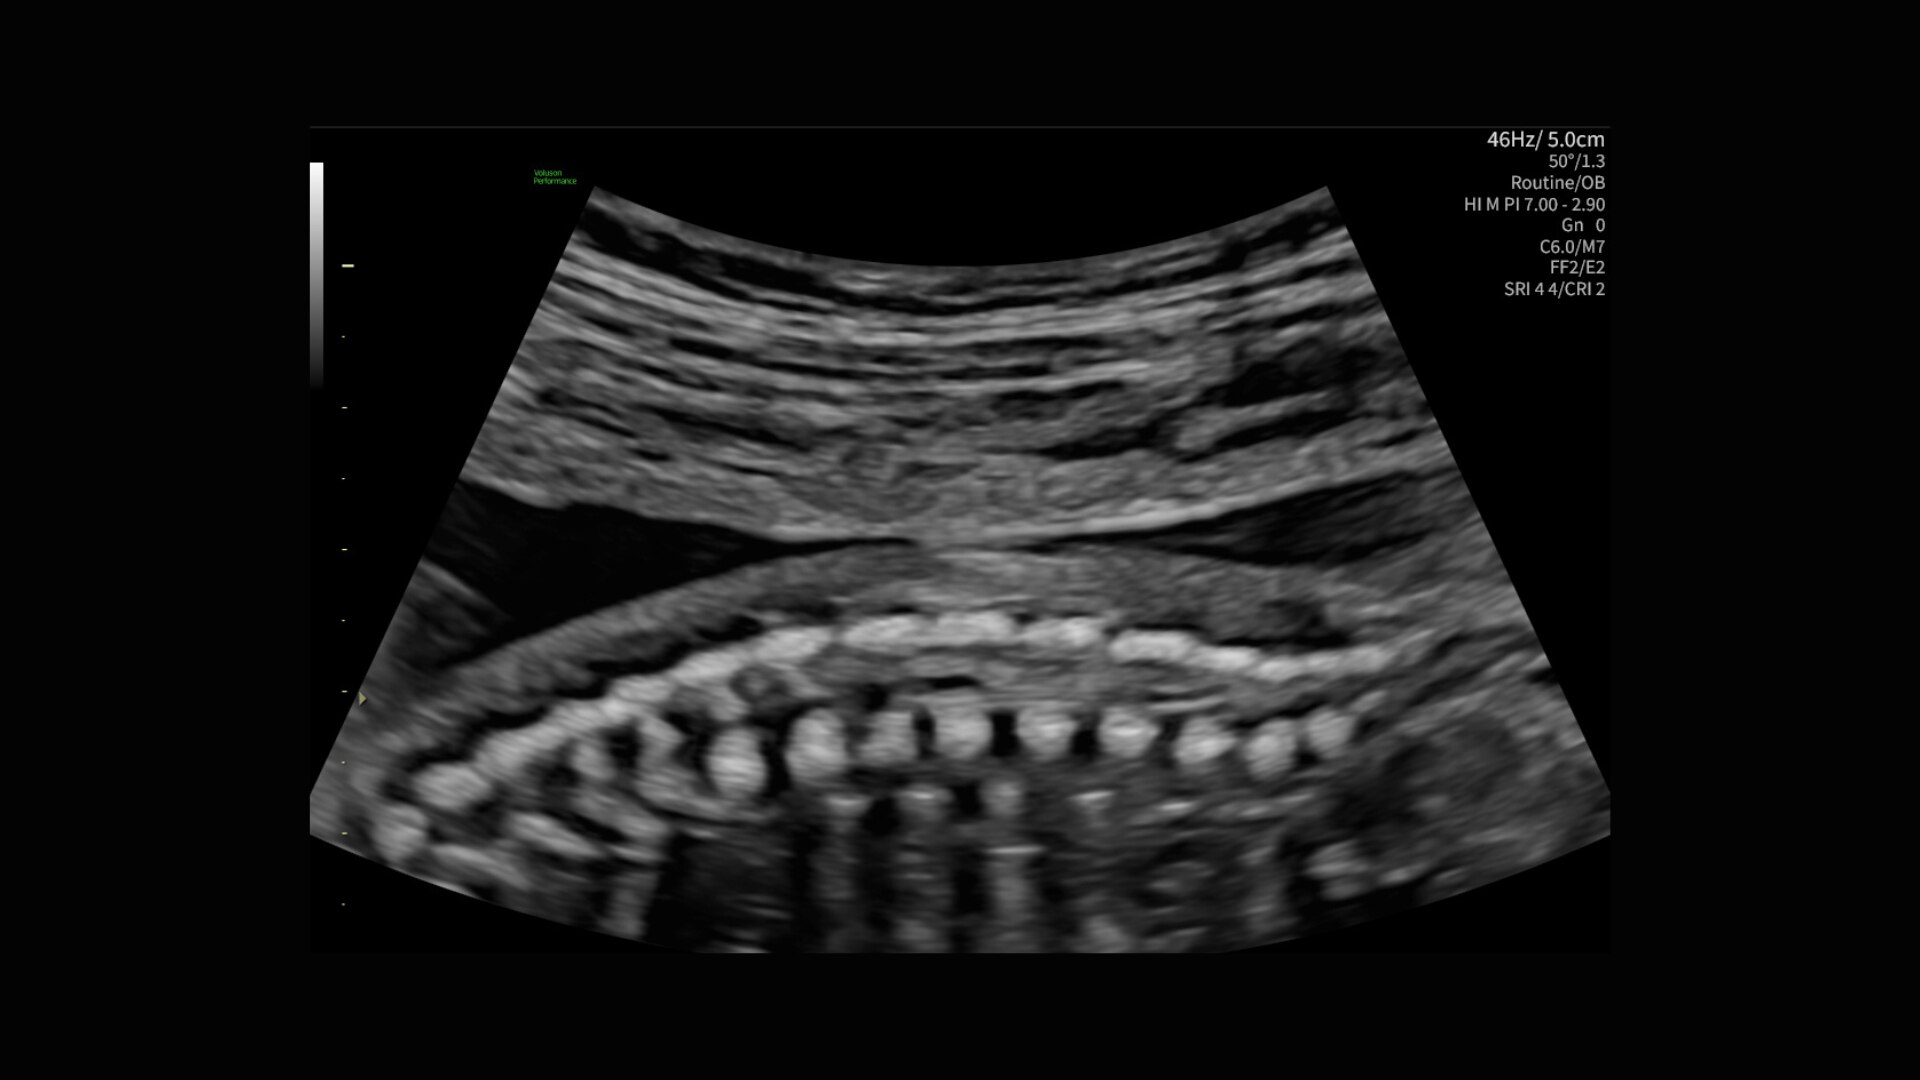

Radiantflow™

Fast, easy 3D-like blood flow visualization

Radiantflow delivers exceptionally sensitive, next level color Doppler for easy fast visualization of blood flow revealing even the tiniest vessels.